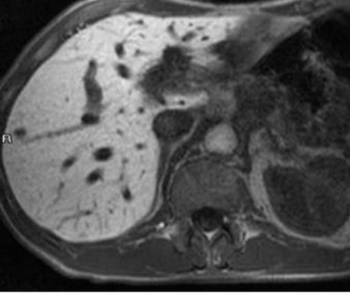

For post-op monitoring of patients who had pancreatic ductal adenocarcinoma (PDAC) resection, a new study showed that diffusion-weighted magnetic resonance imaging (MRI) had enhanced sensitivity for detecting recurrent tumors in comparison to conventional MRI.